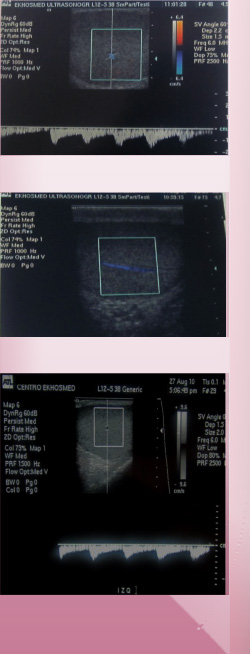

La ecografía Doppler testicular es muy útil en la valoración de una torsión testicular, en la cual el flujo de sangre al testículo afectado se puede reducir.

Permite evaluar  varicocele o  dilatación del plexo venoso peri testicular